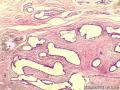

乳腺包块

性别年龄43临床诊断

一般病史发现右乳包块1月,B超示纤维瘤

标本名称乳腺包块

大体所见灰包色栓线包块一个,直径1.3cm,切面灰白、质中,包膜完整,

纤维腺瘤